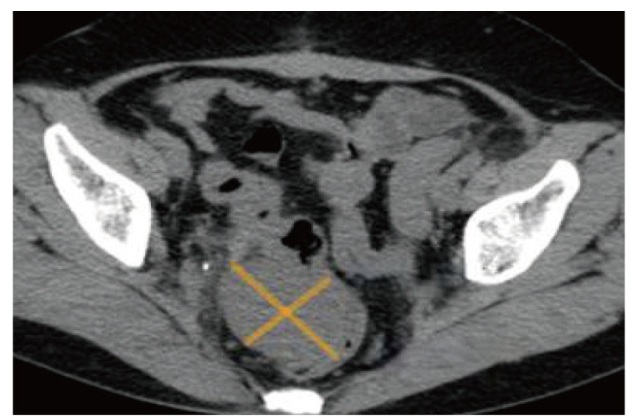

报告1例原发于宫颈的未分化子宫肉瘤病例。患者因绝经7年,阴道出血1周就诊,妇科检查触及宫颈9 cm大小的肿物,影像学检查提示宫颈巨大肿物及盆腔积液,未见明显肿大的淋巴结。遂行经腹全子宫切除术+双侧输卵管卵巢切除术,术后病理活检及免疫组织化学检查提示低级别未分化子宫肉瘤。术后患者拒绝放化疗,未定期复查。半年后再次因阴道出血,下腹部胀痛就诊,影像学提示阴道残端占位性病变,考虑肿瘤复发可能,遂行经导管髂内动脉栓塞术+髂动脉造影+动脉注射化疗药物(顺铂60 mg+表柔比星30 mg)。2个月后又因间断阴道出血在外院化疗1次。定期随访9个月,期间未行治疗,间断阴道出血。后失访。

A case of primary undifferentiated uterine sarcoma of the cervix is reported. The patient presented for medical consultation due to vaginal bleeding for 1 week after 7 years of menopause. A 9 cm mass in the cervix was detected during a gynecological examination. Imaging studies indicated a huge cervical mass and pelvic effusion, with no obvious enlarged lymph nodes. Subsequently, an abdominal total hysterectomy and bilateral salpingo-oophorectomy were performed. Postoperative pathological biopsy and immunohistochemistry suggested low-grade undifferentiated uterine sarcoma. After the operation, the patient refused radiotherapy and chemotherapy and did not undergo regular follow-up. Six months later, the patient presented again with vaginal bleeding and lower abdominal distension and pain. Imaging showed a space-occupying lesion at the vaginal stump, and tumor recurrence was considered possible. Therefore, transcatheter internal iliac artery embolization, iliac artery angiography and intra-arterial injection of chemotherapy drugs (cisplatin 60 mg + epirubicin 30 mg) were carried out. Two months later, the patient received chemotherapy once at another hospital due to intermittent vaginal bleeding. The patient was followed up regularly for 9 months, during which no treatment was administered, and intermittent vaginal bleeding occurred. The patient was then lost to follow-up.